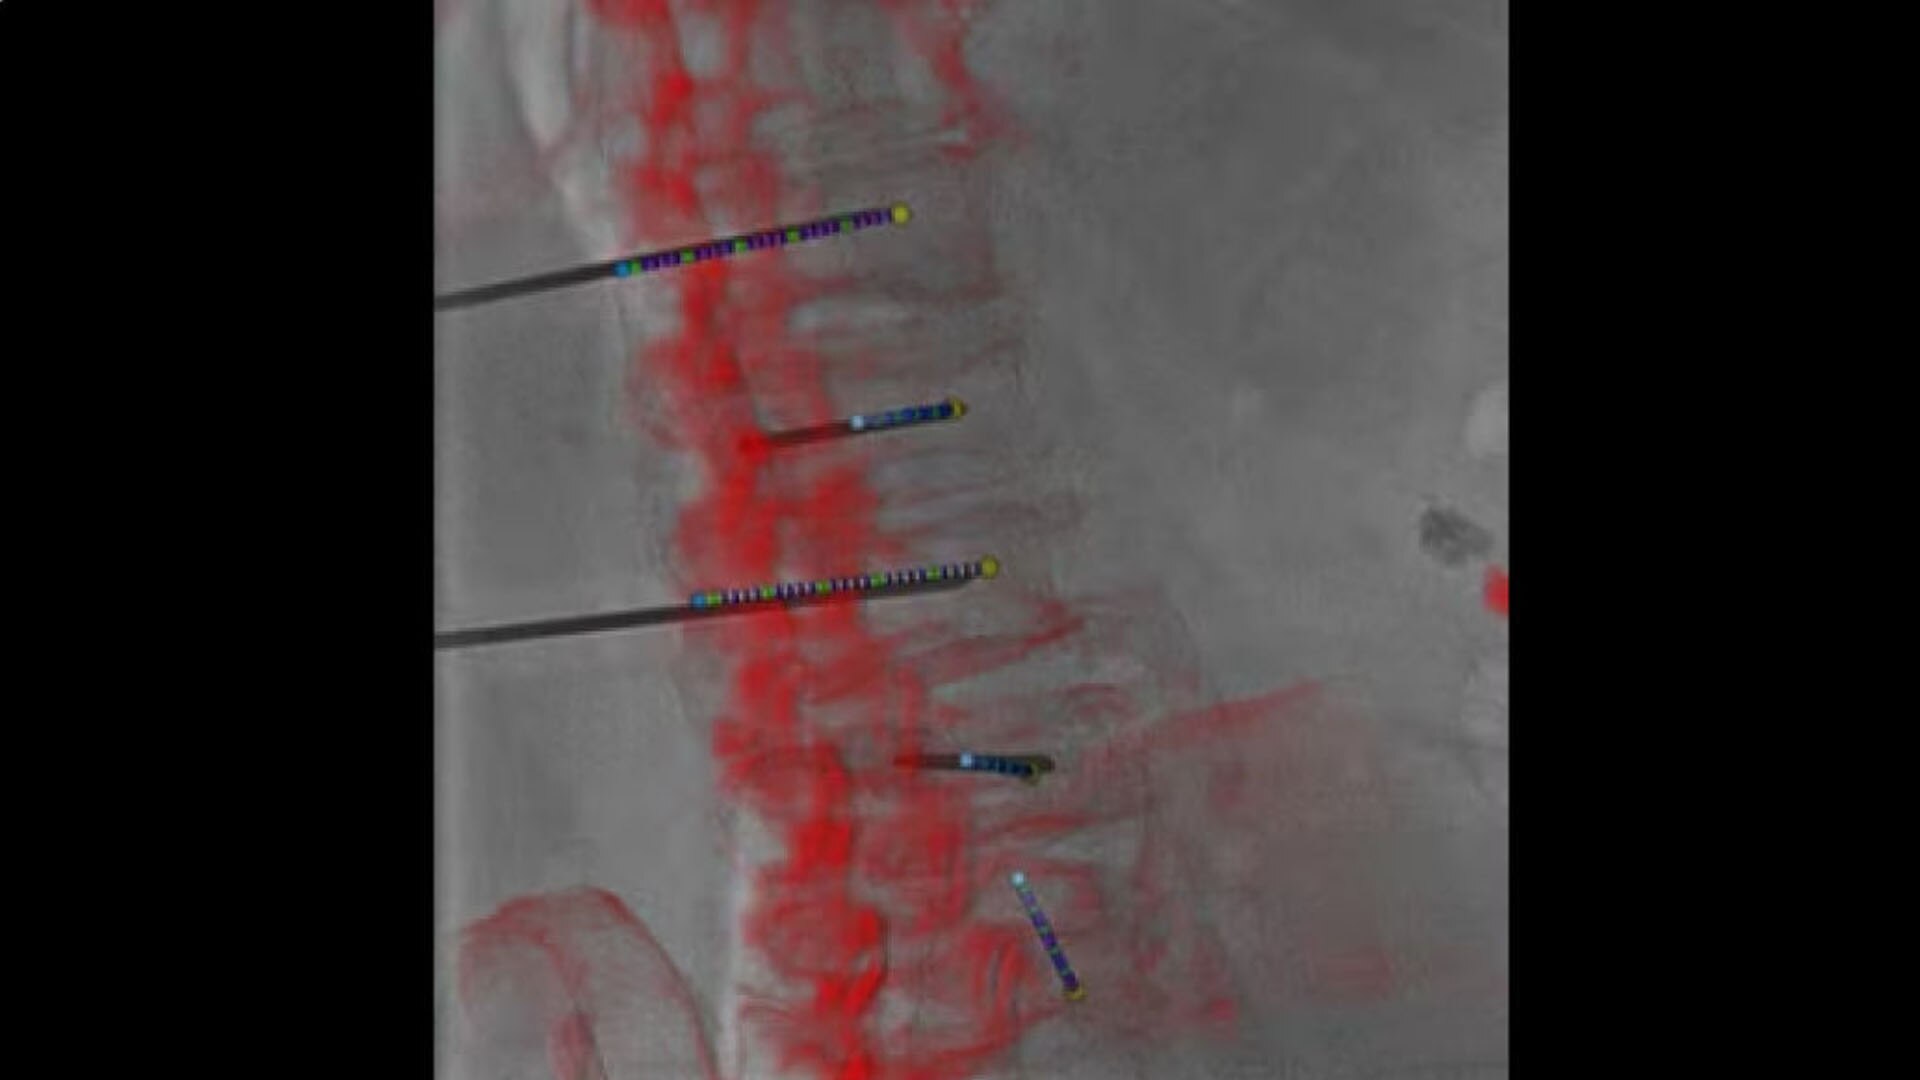

Access

Review needle placement

All at table side, reconstruct a needle in 3D with 2 fluoroscopic images with accuracy and to review the location of the reconstructed needle on the 3D anatomy.